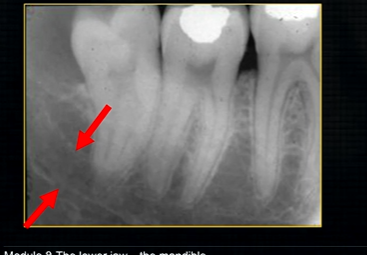

mental foramen - black radiolucency - near 1st and 2nd premolars

sockets of the teeth are represented by thin, white, opaque lines → ‘ lamina dura’

dense, white, radiopaque line → dense bone of mylohyoid ridge

underneath mylohyoid ridge - looks more radiolucent → this is due to the lingual indentation of submandibular fossa

dense cortical bone of the lower border